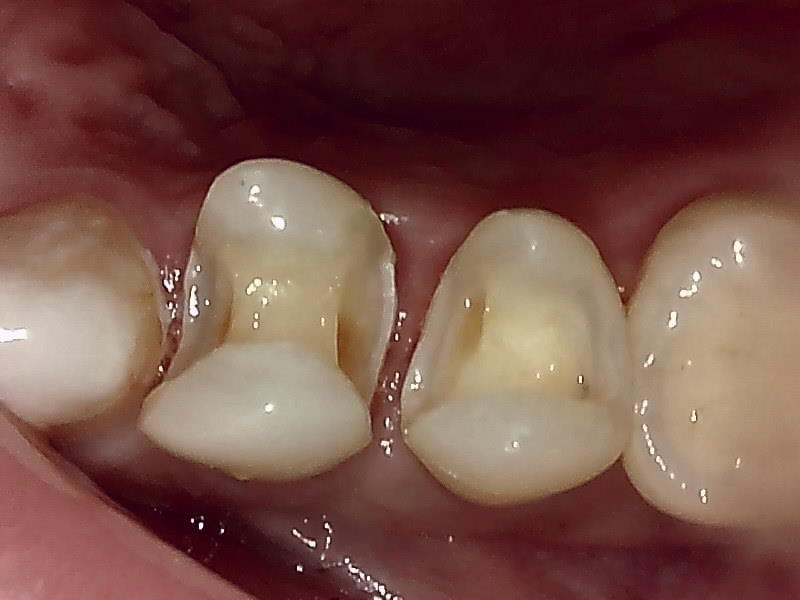

セラミックインレーの装着前の窩洞形成(写真)